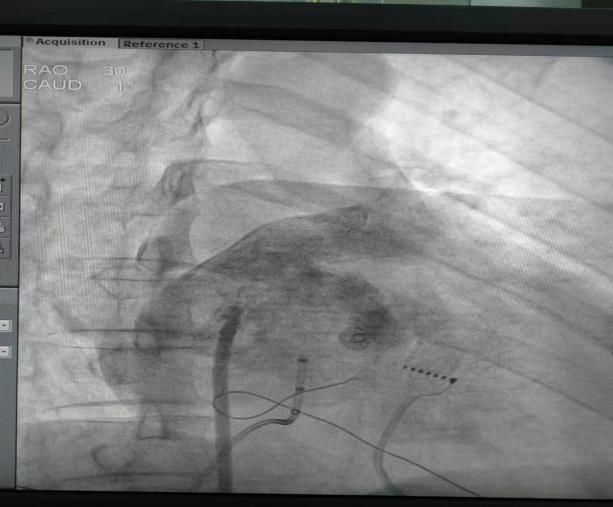

(9) 2018年11月12日开展第一例心脑联合术。

患者:梁某 男性 60岁 青屏办事处

图片

术前

术后